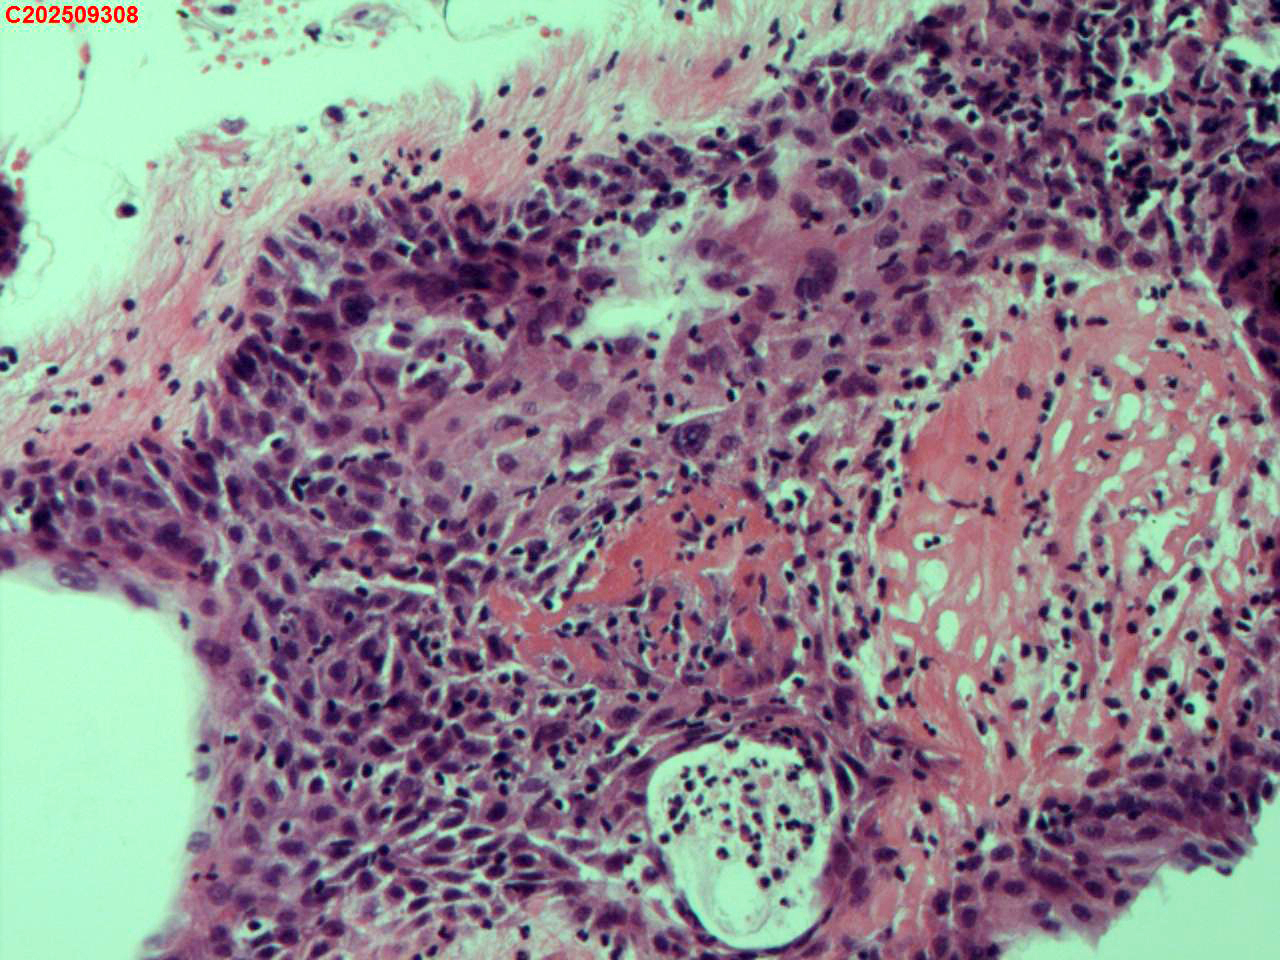

纤支镜咬检

肺结核、气管结核?

胸部CT:左肺多发病变及空洞考虑结核,请结合其他相关检查。右肺上叶小点状钙化灶。左肺门增大。

纤支镜:肉芽增生

送检粘膜鳞状上皮增生伴炎性渗出物及坏死物,建议做抗酸染色排除结核

上下细胞一致,我要标记下????